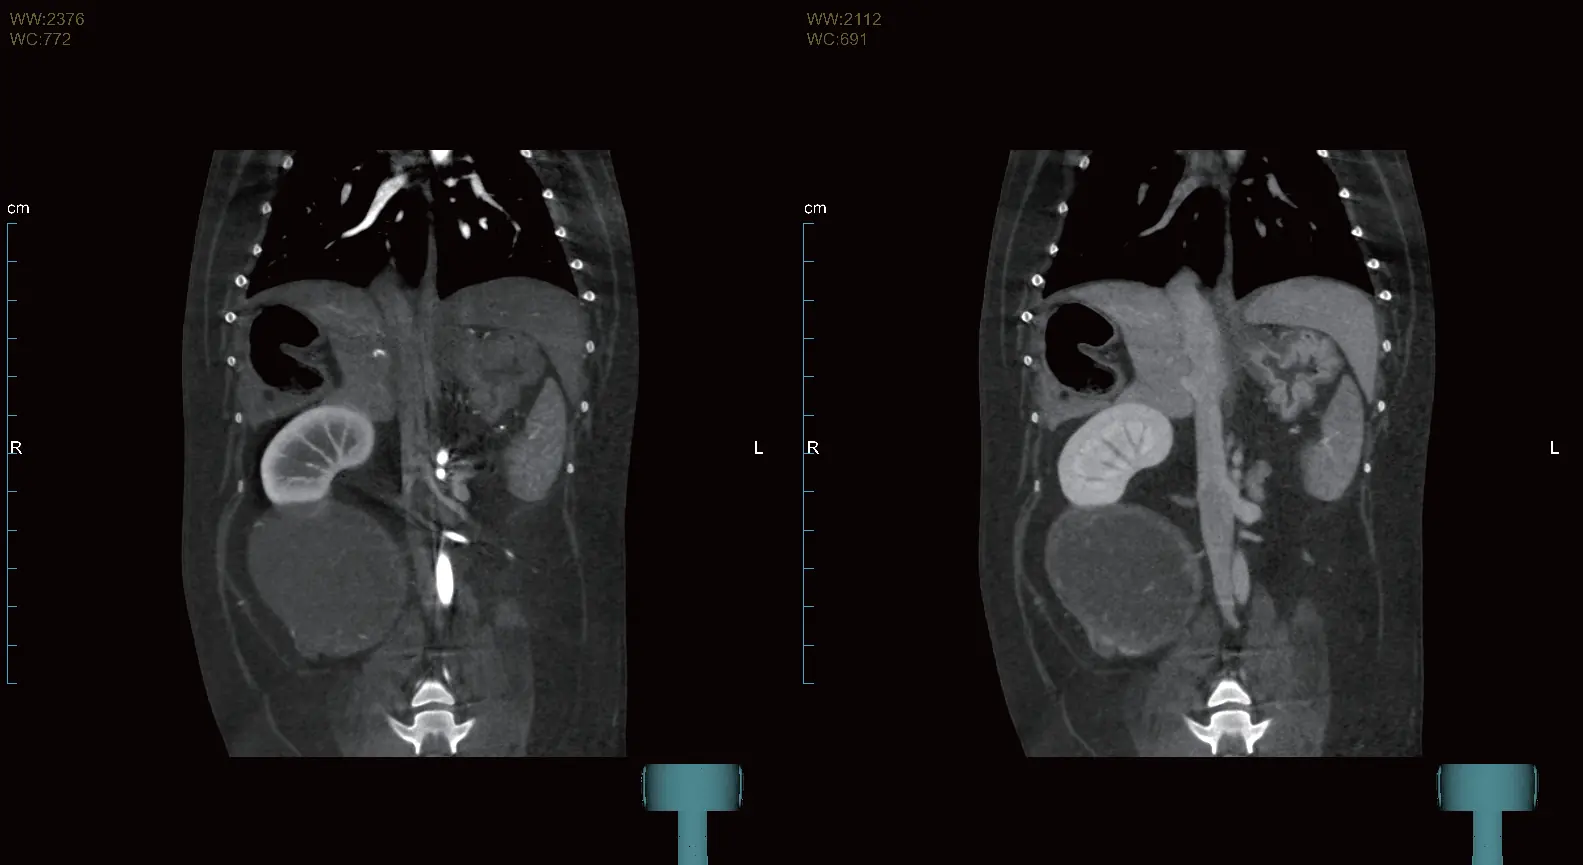

Simetrik prostat büyümesi ile birlikte homojen kontrastlanma. Halka şeklinde kontrastlanan çok sayıda kistik yapı. Büyümüş internal ve eksternal iliak lenf düğümleri.

Arteriyel, venöz ve geç fazları tek bir taramada otomatik olarak kaydeder. İş akışını kolaylaştırır ve fazlar arası karşılaştırmaya imkân tanıyarak lezyonların daha net ve verimli şekilde saptanmasını sağlar.